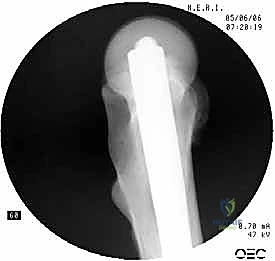

2. الرد المغلق (Closed Reduction)

باستخدام جهاز الأشعة السينية المرئية المستمرة (C-Arm Fluoroscopy) داخل غرفة العمليات، يقوم الدكتور هطيف بإعادة العظام المكسورة إلى محاذاتها التشريحية الصحيحة عن طريق الشد والتدوير الخارجي للساق، وكل ذلك يتم مراقبته على الشاشة بدقة متناهية.

4. توسيع القناة وإدخال المسمار

يتم استخدام أدوات حفر خاصة (Reamers) لتوسيع القناة النخاعية بلطف لتستوعب المسمار المصنوع من التيتانيوم. بعد ذلك، يتم انزلاق المسمار النخاعي الرئيسي داخل العظم حتى يصل إلى العمق المطلوب.